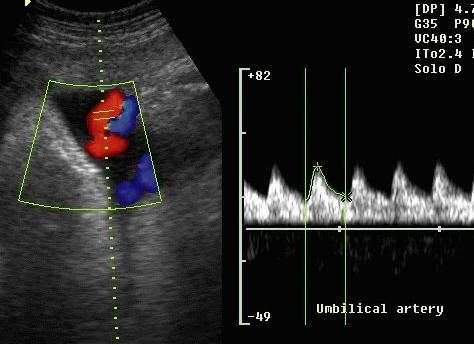

пример кадра триплексного допплерометрического обследования

Триплексное исследование более современно и дает больше информации о кровотоке. Получаемое цветное изображение показывает кровоток и его направление. Врач видит на мониторе красные и синие потоки, а обывателю может показаться, что это движется артериальная и венозная кровь. На самом деле, цвет в данном случае говорит не о составе крови, а о ее направлении – в сторону датчика или от него.